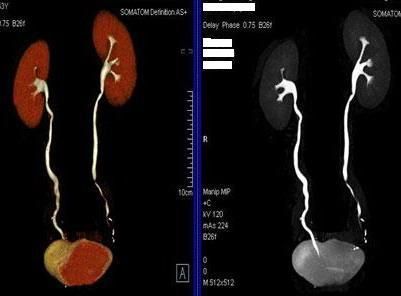

四、全尿路成像及骨關節三維成像。

全尿路成像(CTU):